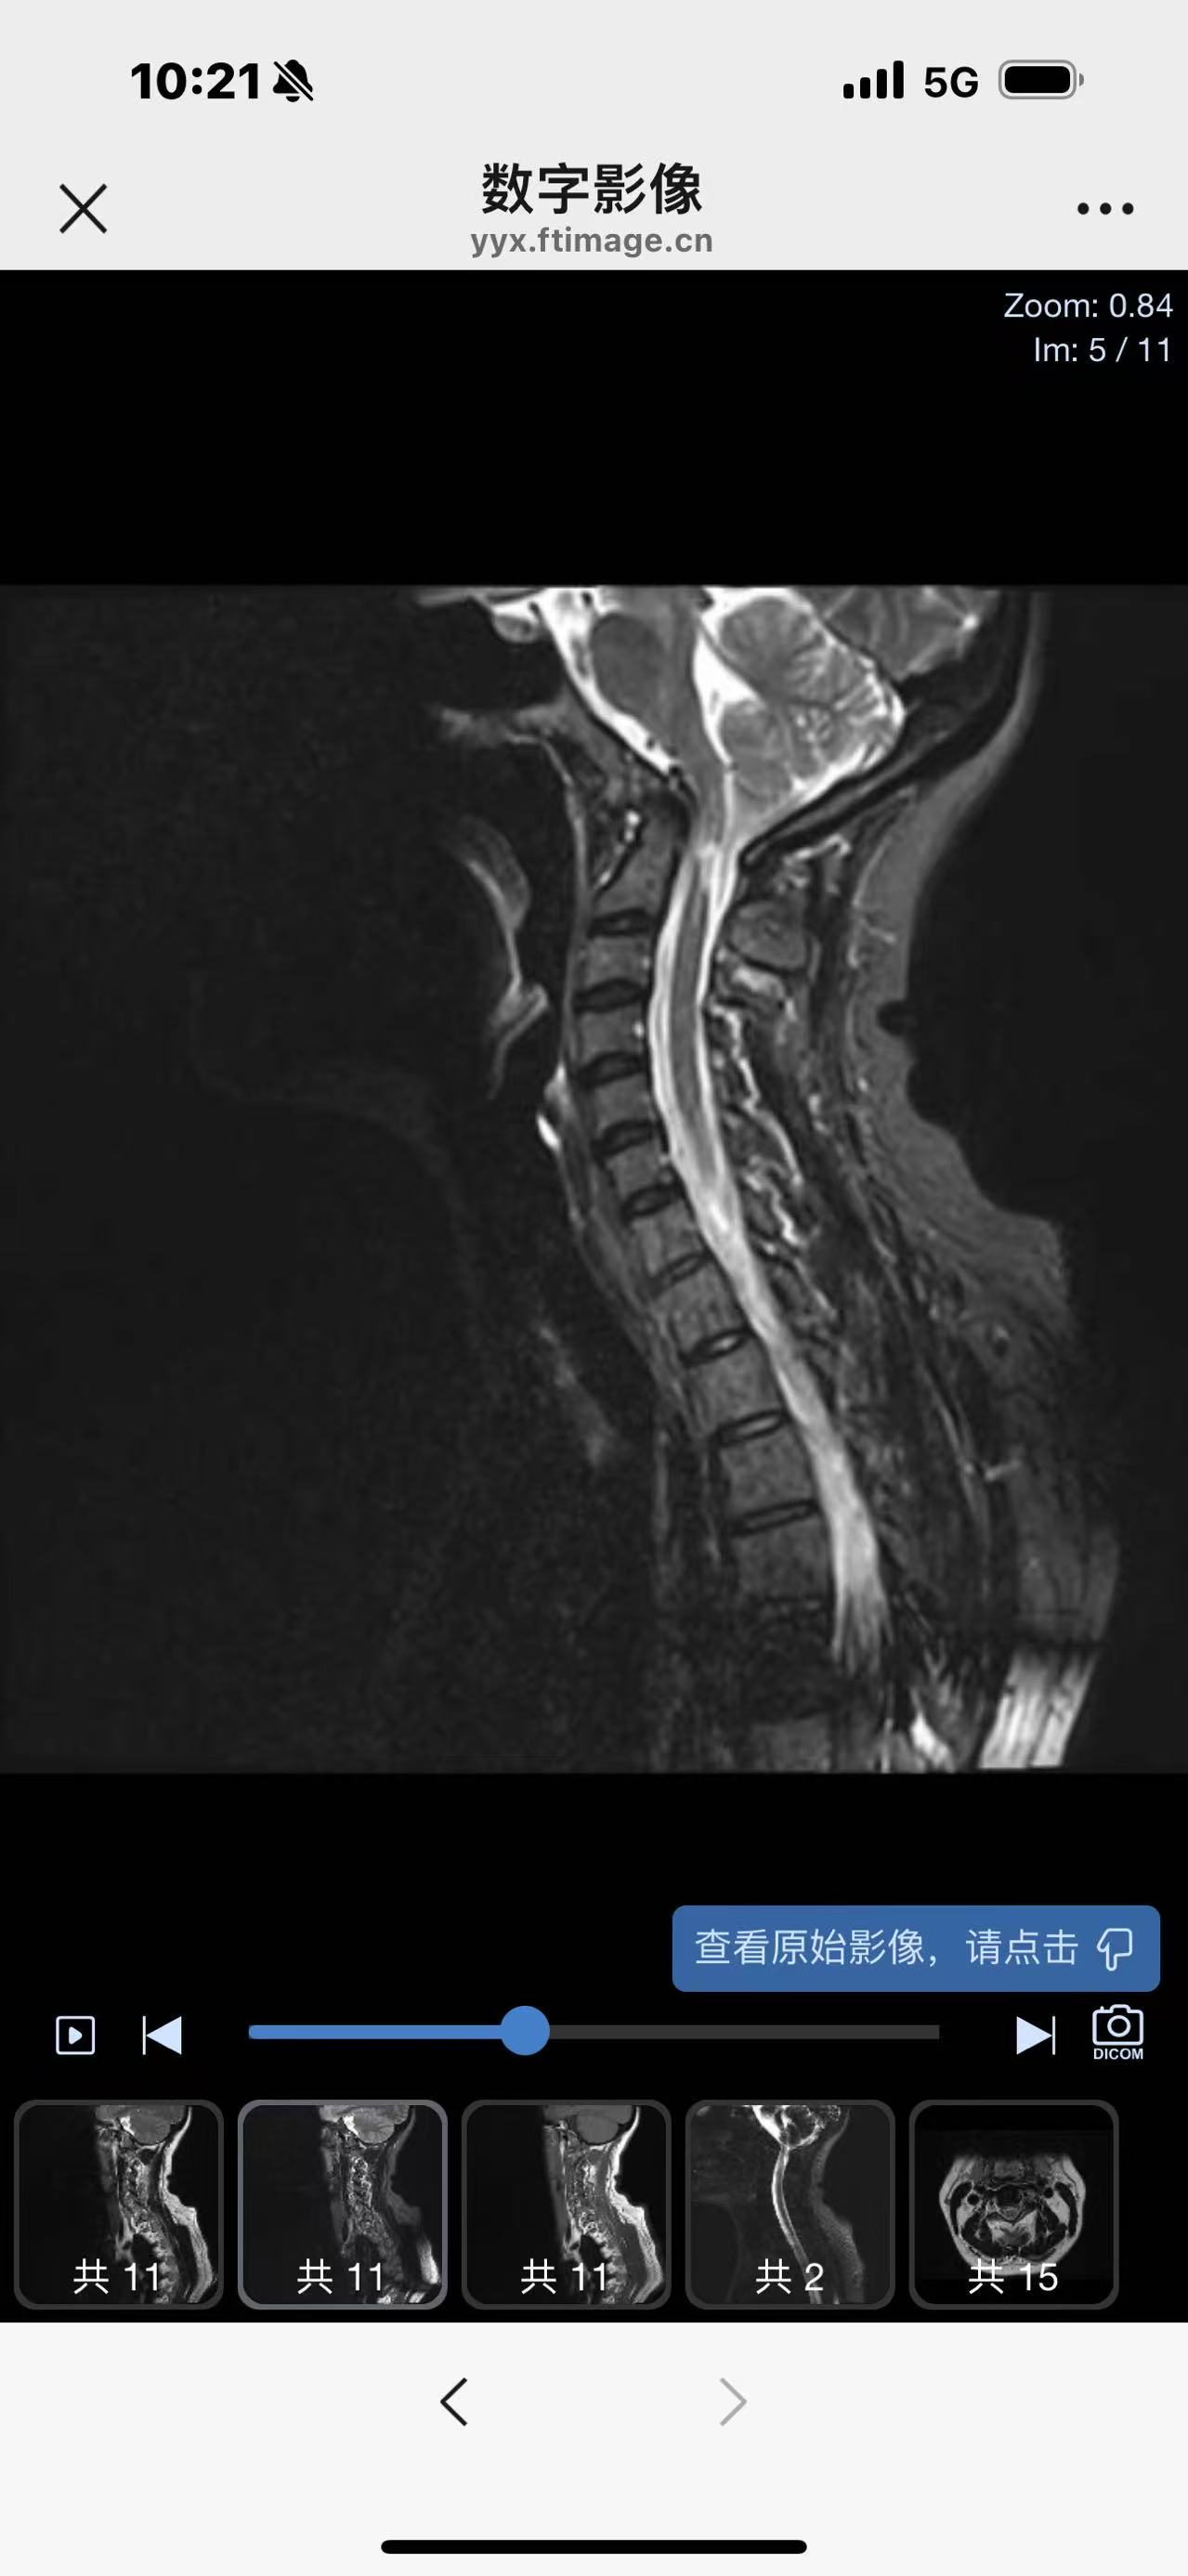

• 诊断:寰枢椎脱位

• 术后状况:没有复位

• 术后影像: